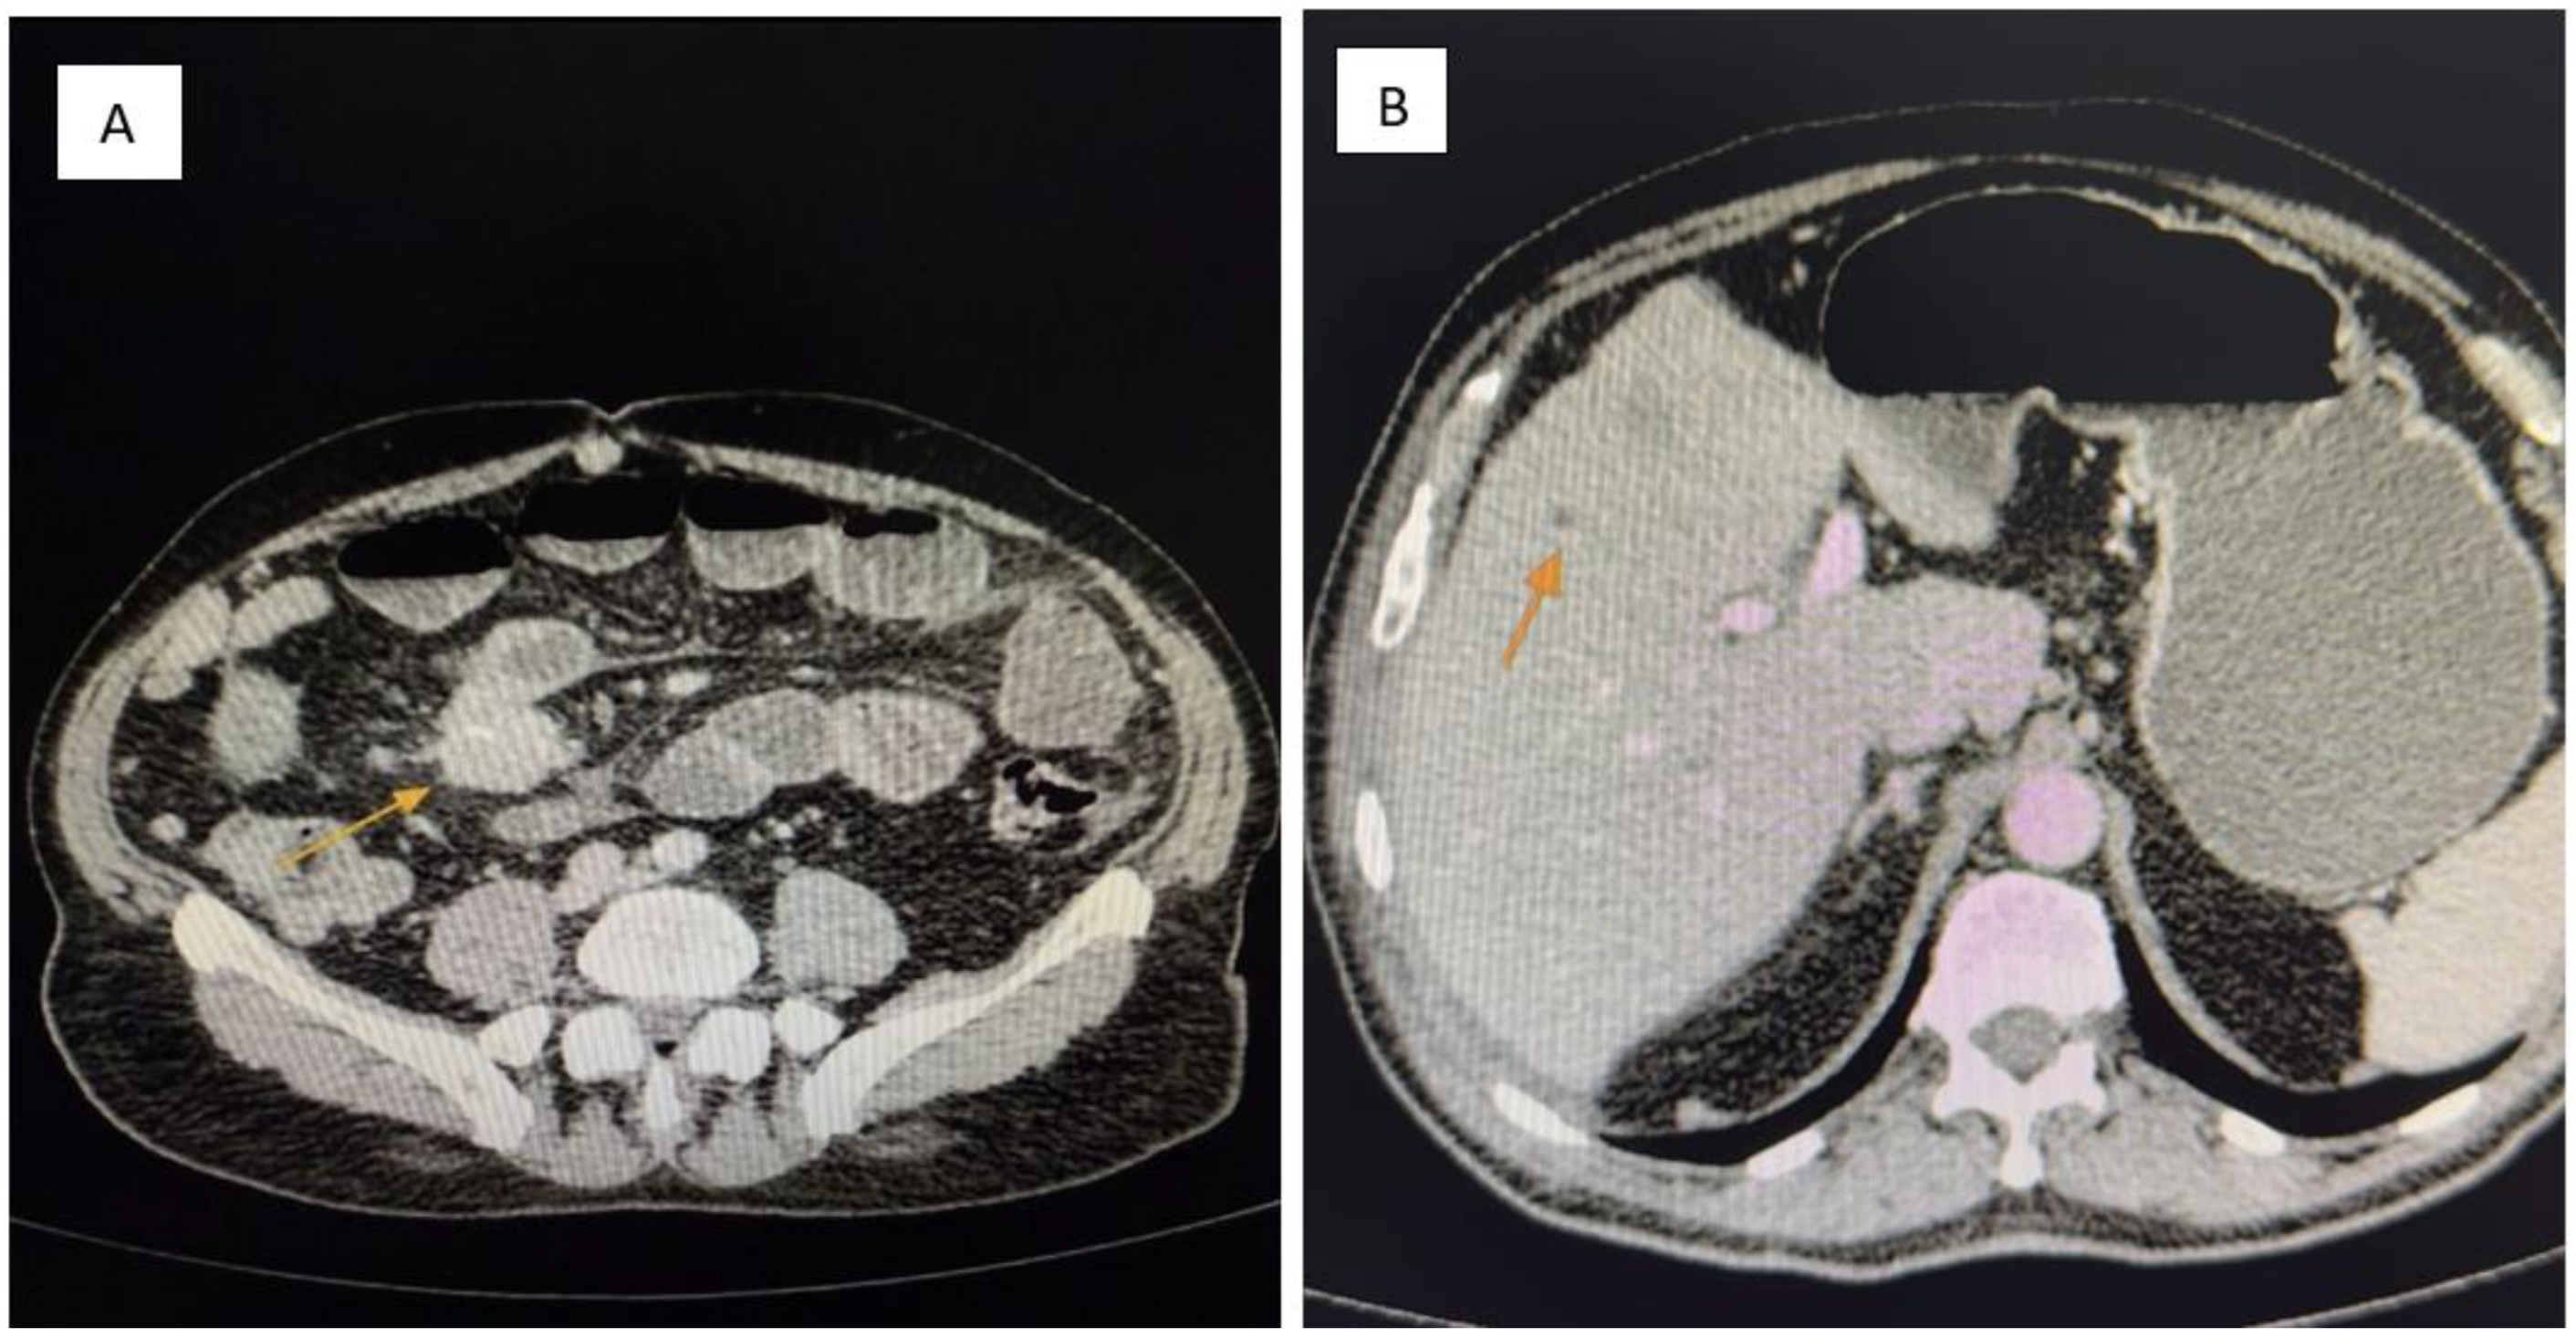

3.4. Diagnostic Assessment

Laboratory investigations showed leukocytosis (WBC 18,000/mm3), elevated C-reactive protein (CRP 65 mg/L), mild electrolyte imbalance (hypokalemia, hyponatremia), and moderate anemia (Hb 10.2 g/dL). Liver function tests and renal function were within normal limits. Tumor markers CEA and CA 19-9 were not elevated at admission but chromogranin A was not available emergently. Contrast-enhanced abdominal and pelvic CT (Siemens Healthineers, Erlangen, Germany) revealed the following:

• A 5 cm mesenteric mass in the pelvic region (Figure 1A).

• Multiple hypodense hepatic nodules compatible with liver metastases (Figure 1B).

• Markedly dilated loops of jejunum and ileum with wall thickening and multiple air–fluid levels.

• Significant ascites and diffuse peritoneal nodular thickening suggestive of carcinomatosis (Figure 2).

Figure 1. (A,B): Contrast-enhanced abdominal CT. (A) A pelvic mesenteric tumor mass (yellow arrow) is seen causing significant dilatation of adjacent small bowel loops, suggestive of partial obstruction. (B) Multiple hypodense hepatic lesions (yellow arrow) are visualized, consistent with secondary metastatic deposits from a neuroendocrine tumor.